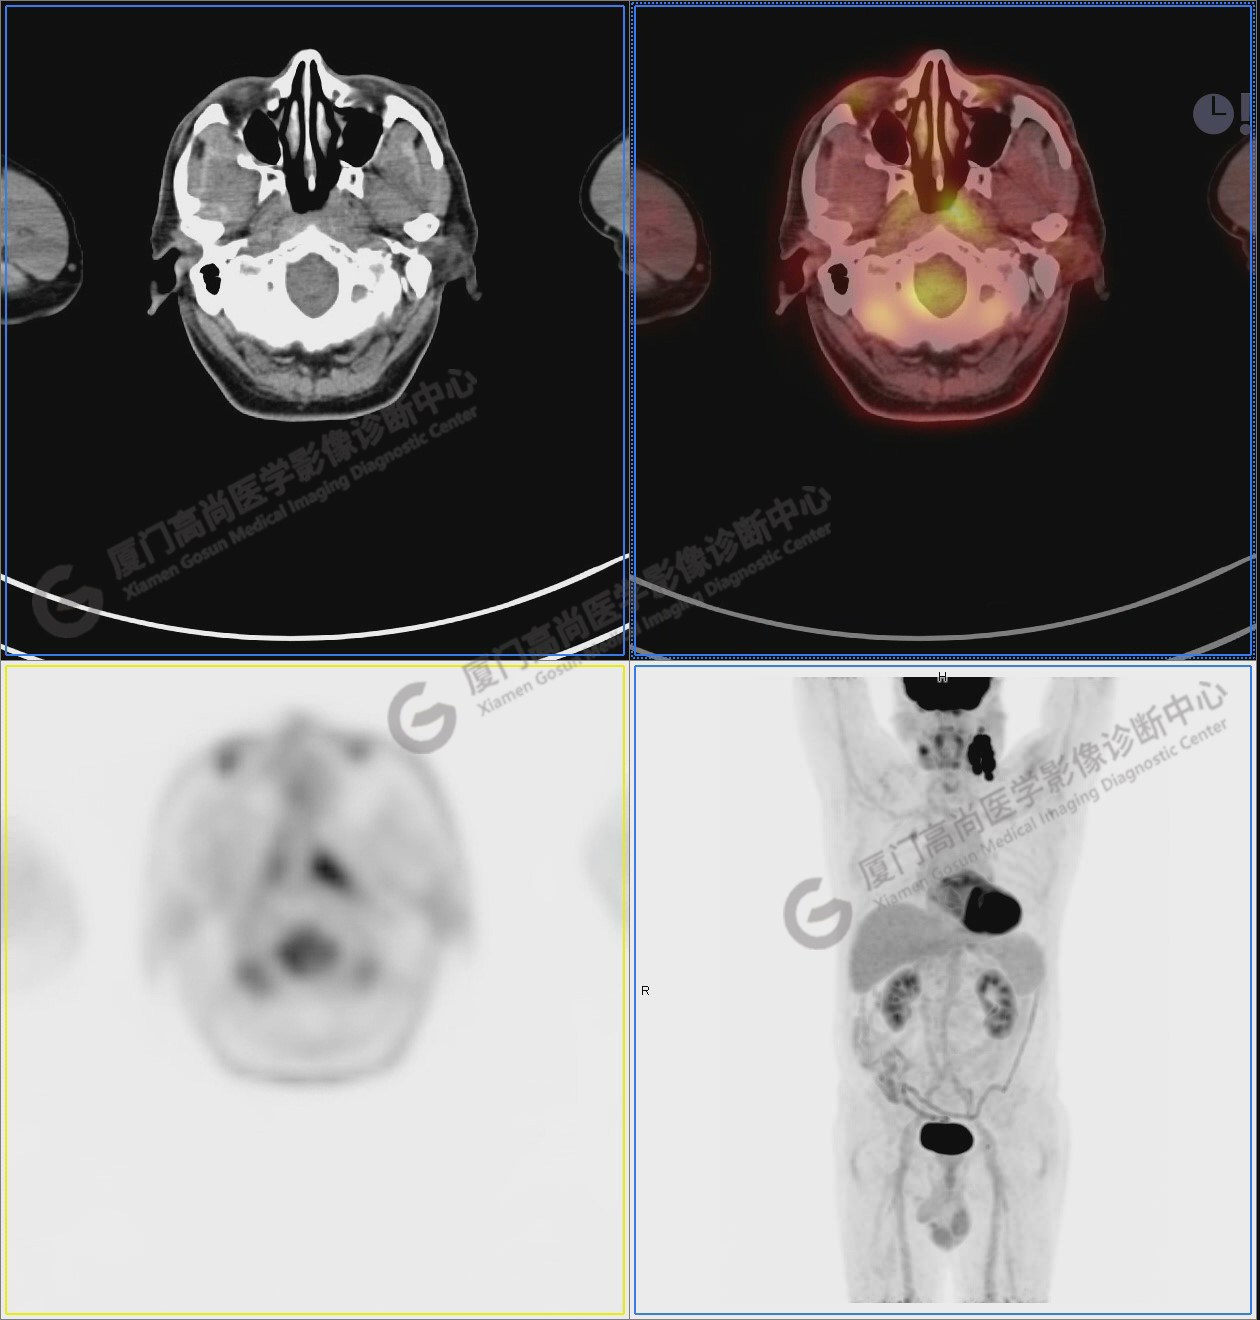

圖1:PET/CT全身圖像

圖2:雙側(cè)頸部多發(fā)增大淋巴結(jié),代謝不同程度增高,考慮為轉(zhuǎn)移。